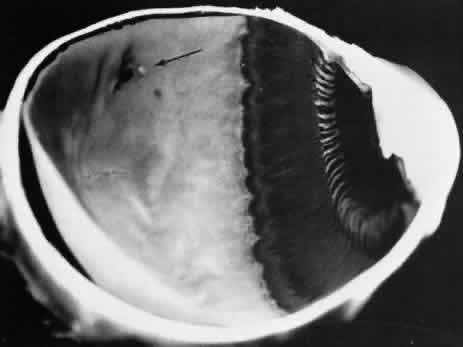

ZONULAR-TRACTION RETINAL TUFT

The zonular-traction retinal tuft always projects from the retinal surface internally and anteriorly toward the zonule (Fig. 40). Usually single and located within the vitreous base, zonular-traction retinal tufts are joined to zonular fibers at the apex; the tufts, which vary in length and thickness, are associated with a broad range of trophic and tractional alterations at the retinal end of the process. Histopathologic changes include zonular attachments at the apex, neuroglial cells within the tuft, and degeneration with retinal thinning at the base (Fig. 41). Retinal holes and tears result from the combination of trophic changes at the base and traction resulting from zonular fibers. Within the vitreous base and posterior to it, zonular-traction tufts may be associated with partial-thickness or full-thickness retinal tears that can occur in the absence of posterior vitreous detachment.

Fig. 40. Zonular-traction tuft of the peripheral retina. Tuft is drawn at an acute angle from the retinal surface toward the ciliary body and shows microcystic degeneration anteriorly. Posteriorly, the tuft splays; the retina at its base shows marked trophic change, including three full-thickness holes (arrow). (× 20.)

Fig. 41. Zonular-traction tuft (arrow) drawn at an acute angle from the retinal surface toward ciliary body with dense-staining glial cells along surface. Base of tuft is microcystic and has full-thickness trophic hole. (Hematoxylin-eosin; × 150.)

Zonular-traction tufts are present at birth and detected with equal frequency in patients of all ages; they are noted in 15% of patients, are bilateral in 15% of affected people, and thus are evident in 9% of all eyes (see Table 3). These tufts are most common in the nasal quadrants, usually attached to the retina less than 0.5 mm posterior to the ora serrata and only infrequently attached to the retina posterior to the vitreous base.27,36

Clinical examination of the peripheral fundus reveals zonular-traction tufts in patients of all ages. These lesions are distinguished from noncystic and cystic retinal tufts by their greater size, sharp anterior angulation, and close proximity to the ora serrata. Zonular-traction tufts are a significant cause of small, round retinal holes in the extreme periphery of the retina. Although retinal holes within the vitreous base are considerably less likely to produce retinal detachment than holes posterior to the vitreous base, surgical aphakia or pseudophakia, which necessarily involves some form of zonular traction, is associated with an increase in the frequency of retinal detachment, which is likely to be related to small retinal breaks in the nasal periphery.36,37